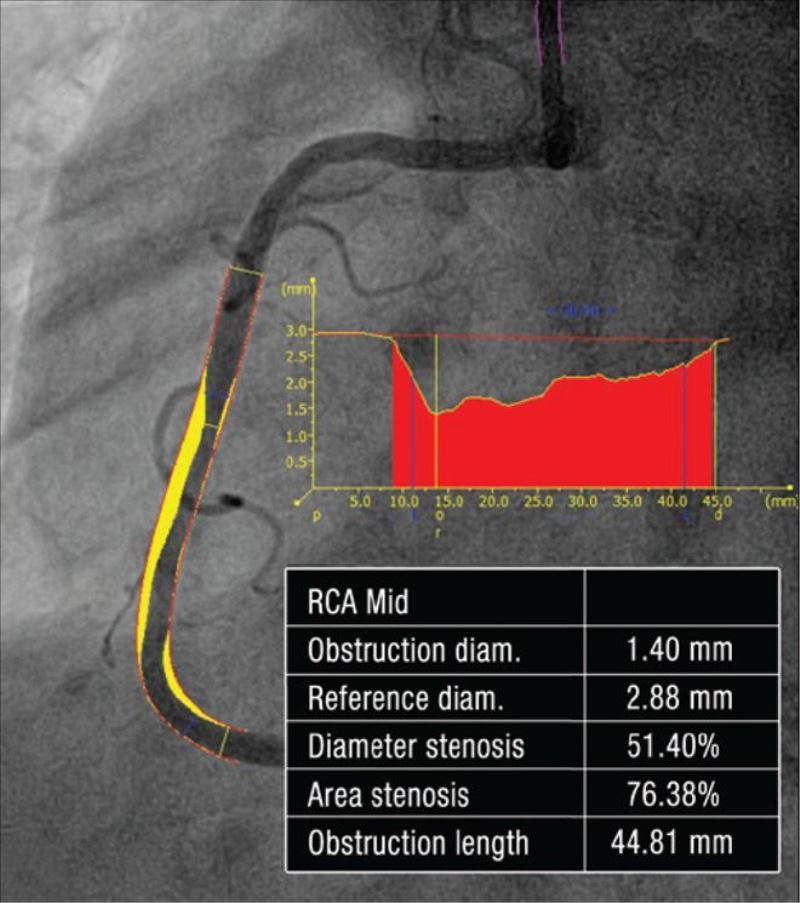

Koroner anjiyografi kalp damarlarını görüntülemek için kullanılan bir tanı yöntemidir. Kalp atar damarlarında daralma, tıkanıklık veya başka bir anomali olup olmadığını göstermek için kullanılır. Kalbin damarlarının görüntülenmesi ve nasıl tedavi edileceği hakkında karar vermek için seri filmler çekilerek görüntüler alınır ve sonucuna göre normal çıkarsa medikal takip,  darlık var ise koroner girişim (balon, stent) veya bypass kararı alınır.